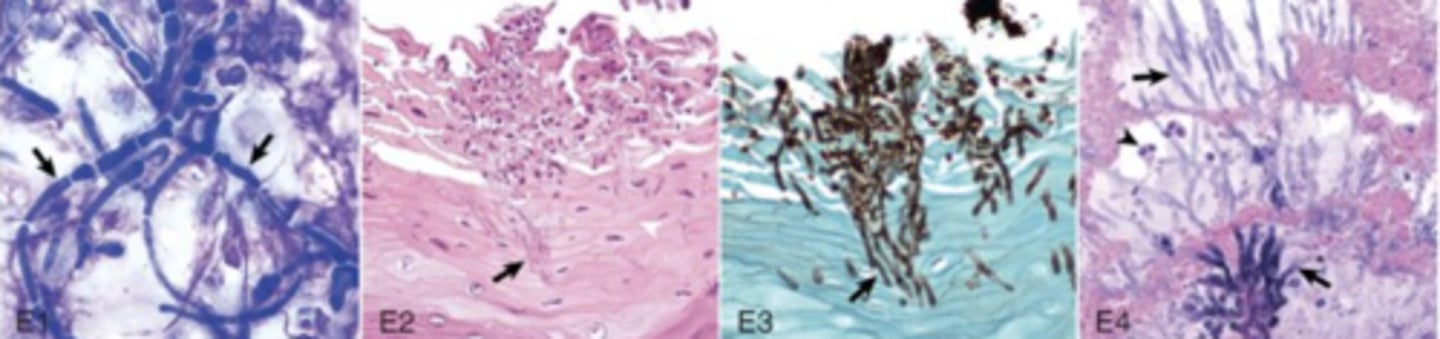

LPS

What type of virulence factor is used by actinobacillus ligneresi to cause this pyogranulomatous inflammatory response?

Fungi

What broad group of pathogens does these images indicate ?